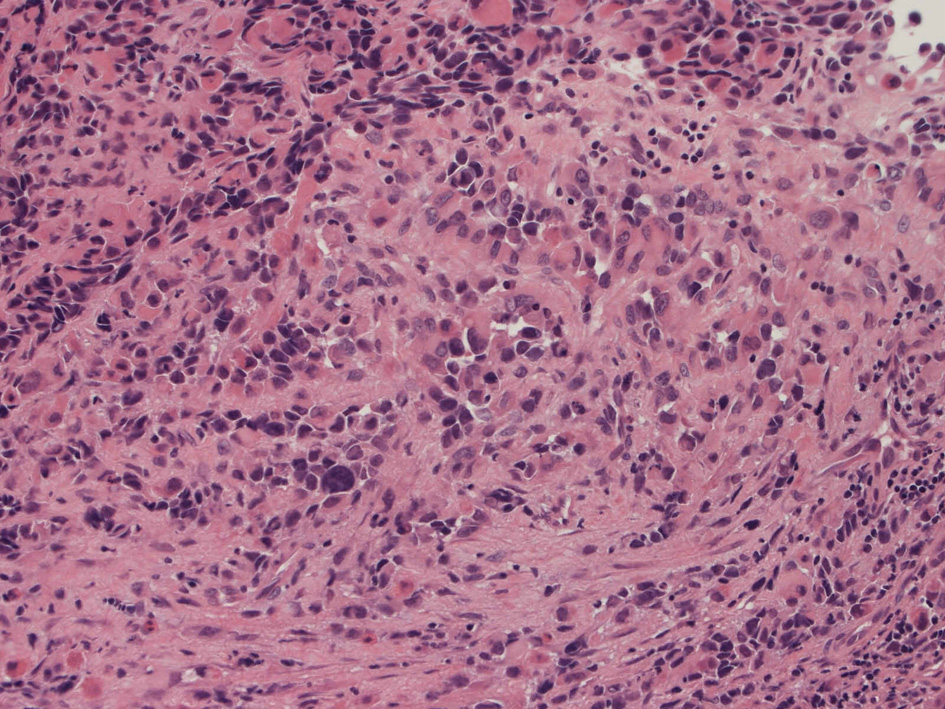

40歳女性 鼻粘膜腫瘤

右頸部のしこりを自覚。近医MRIで頸部多発リンパ節腫大あり当院を紹介される。右顎下, 右鎖骨上窩にも多数のリンパ節を触れる。穿刺細胞診ではcarcinoma疑い。右鼻腔, 上顎洞にも腫瘤が認められリンパ節腫大との関係を調べるために鼻腔腫瘤の生検が行われる。

病理組織所見

small round cell tumorの中でrhabdomyosarcomaは腫瘍細胞に種々の抗原が陽性となるため診断を誤ることがあり注意が必要である*1